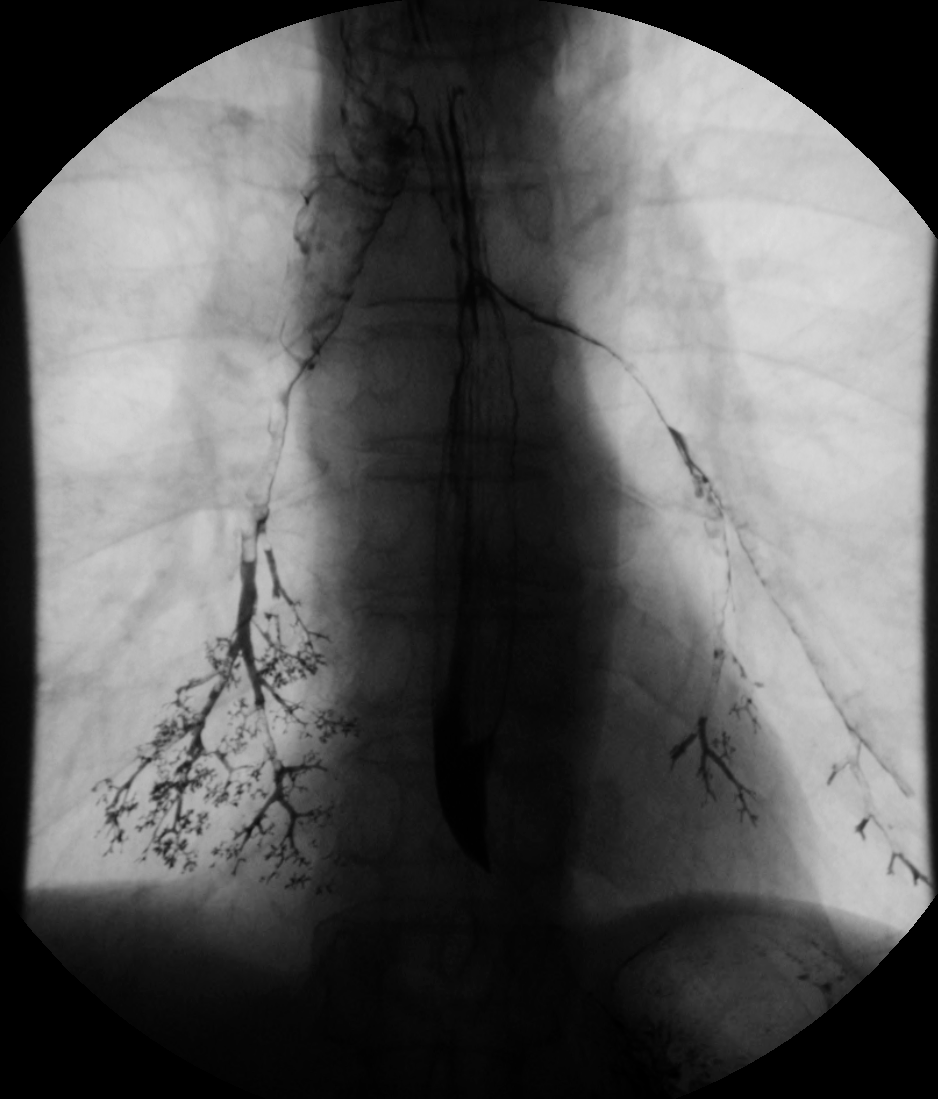

- 경구 투여 중 황산바륨의 흡인 또는 흡입은 심각한 호흡기 합병증을 유발하여 치명적인 흡인성 폐렴 또는 질식으로 이어질 수 있다.[35]